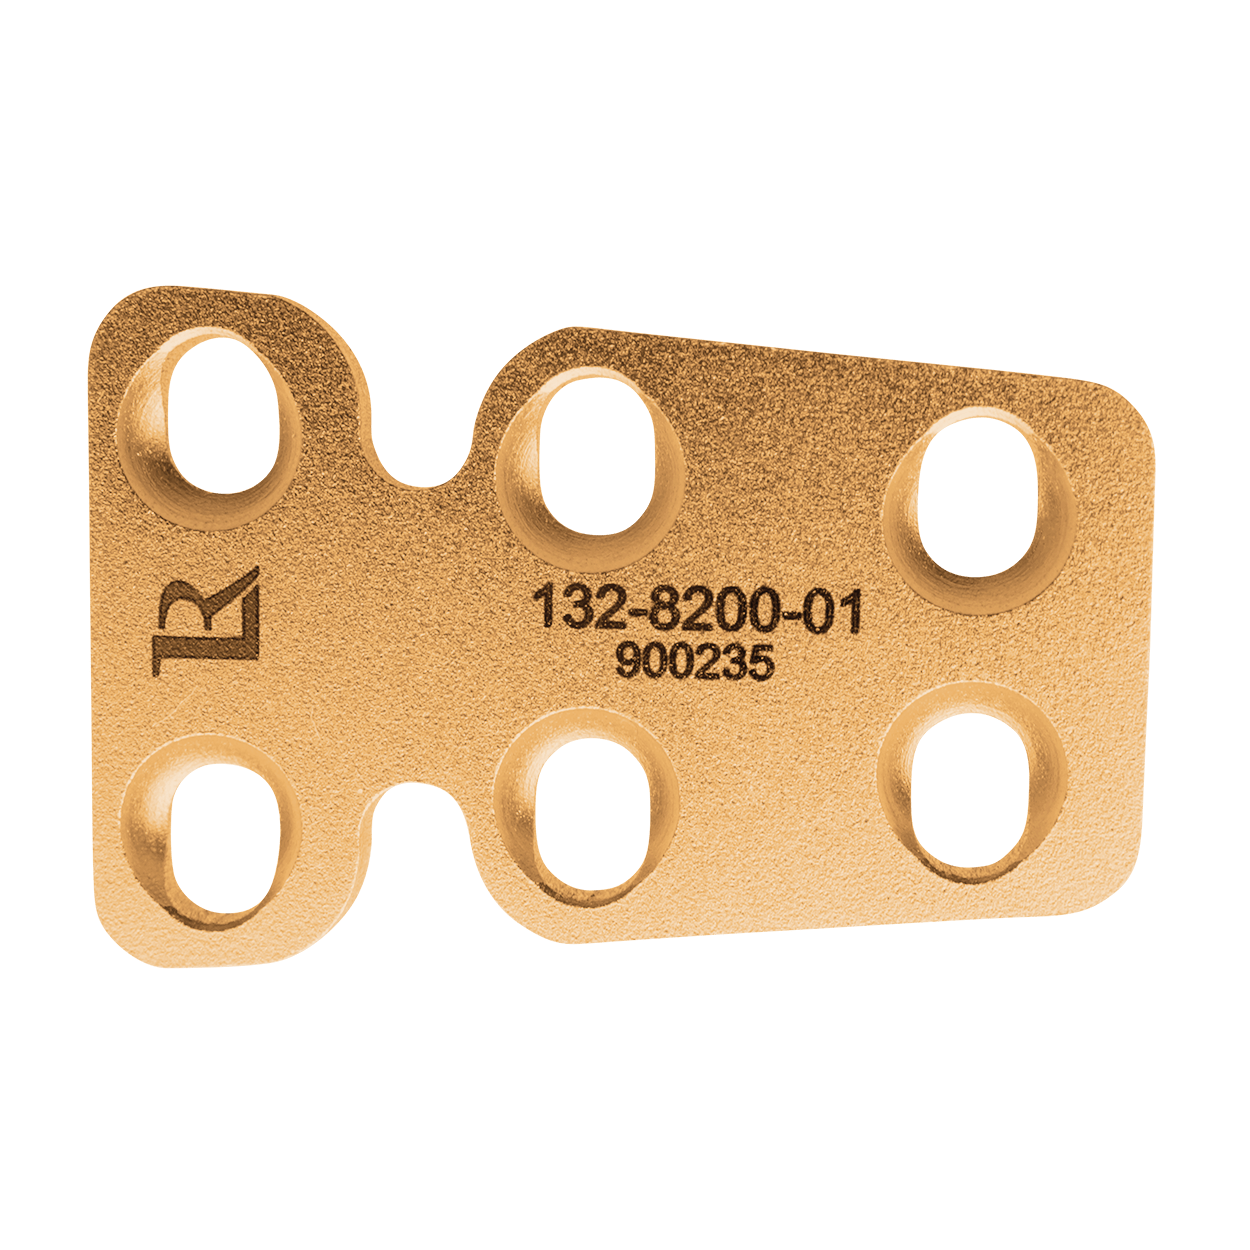

The RAPID Patella Luxation Plates and Spacers constitute a versatile system designed to address patellar luxation across a diverse range of patient sizes and breeds.

Offering three different plate sizes (Petite/Tiny 2.0 mm, Medium 2.4 mm, Large 2.4 mm), and a total of 20 different spacer variations to match the plates, the RAPID Luxation System enables the surgeon to select the appropriate plate and spacer combination to address the unique anatomical challenges presented by each patient.

The RAPID Luxation Implants and Screws are made of medical grade Titanium for best biocompatibility.